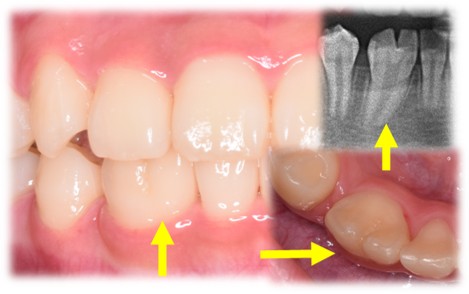

癒合歯

2つの歯胚(歯になる原器)が融合してできたもの。エナメル質、象牙質も癒合し、かつ歯髄(一般的には神経と呼ばれている)も癒合している場合が多いです。

癒合歯がある場合は、上下歯列の真ん中をぴったり一致させるのが難しくなったり、かみ合わせがわずかにずれる(日常生活に支障は出ないレベルでのわずかなずれ)原因になったりすることがあります。